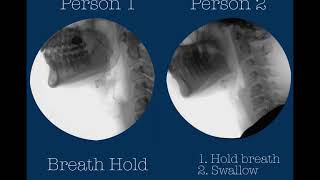

Anatomy & Physiology of swallowing function as narrated by Bonnie Martin-Harris, PhD, CCC-SLP. Swall...